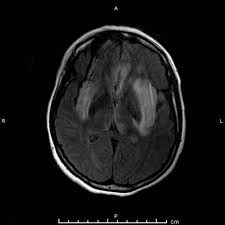

The differential diagnoses include limbic encephalitis (paraneoplastic), gliomatosis cerebri, and status epilepticus. Ventriculitides) refers to inflammation, usually due to infection, of the ependymal lining of the cerebral ventricles. For a general discussion, and for links to other system specific manifestations, please refer to the article on coccidioidomycosis. Herpes simplex (hsv) encephalitis is the most common cause of fatal sporadic fulminant necrotising viral encephalitis and has characteristic imaging findings. Bilateral temporal lobe t2 hyperintensity refers to hyperintense signal involving the temporal lobes on t2 weighted and flair imaging. For a general discussion, and for links to other system specific manifestations, please refer to the article on hydatid disease. Given the history of fever and seizures coupled with the mri findings of bilateral mesial temporal lobe changes, herpes encephalitis requires clinical consideration. It is most often due to meningitis. Multilocularis.the larval stage is the cause of hydatid disease in humans 1. Spinal hydatid disease is an uncommon manifestation of hydatid disease, caused by the larval stage of echinococcus granulosus, or less commonly e. Terminology cerebritis is essentially the same as encephalitis except that it is used to denote brain par. It is a common finding on brain mri and a wide range of differentials should be considered 1. It is usually bilateral but asymmetrical.

Bilateral temporal lobe t2 hyperintensity refers to hyperintense signal involving the temporal lobes on t2 weighted and flair imaging. Multilocularis, and describes a spectrum of disease involving the spinal cord, the spine, or both. It is estimated to occur in ~2% of pati. Hse may result from primary infection or reactivation from latency, and it frequently involves frontal or temporal lobes, as well as the brain stem. This patient went on to have hsv encephalitis proven on csf pcr.

The changes spare the basal ganglia, a feature which is helpful in distinguishing an mca infarct with hemorrhagic transformation from herpes simplex encephalitis, the diagnosis in this case. Hse may result from primary infection or reactivation from latency, and it frequently involves frontal or temporal lobes, as well as the brain stem. Herpes simplex (hsv) encephalitis is the most common cause of fatal sporadic fulminant necrotizing viral encephalitis and has characteristic imaging findings. It is usually bilateral but asymmetrical. The differential diagnoses include limbic encephalitis (paraneoplastic), gliomatosis cerebri, and status epilepticus. Two subtypes are recognized which differ in demographics, virus, and pattern of involvement. Given the history of fever and seizures coupled with the mri findings of bilateral mesial temporal lobe changes, herpes encephalitis requires clinical consideration. Spinal hydatid disease is an uncommon manifestation of hydatid disease, caused by the larval stage of echinococcus granulosus, or less commonly e. Multilocularis.the larval stage is the cause of hydatid disease in humans 1. The differential diagnoses include limbic encephalitis (paraneoplastic), gliomatosis cerebri, and status epilepticus. Herpes simplex encephalitis (hse) is the most common form of viral sporadic encephalitis and, when left untreated, has a mortality rate of 70% (3, 22). This patient went on to have hsv encephalitis proven on csf pcr. Bilateral temporal lobe t2 hyperintensity refers to hyperintense signal involving the temporal lobes on t2 weighted and flair imaging.